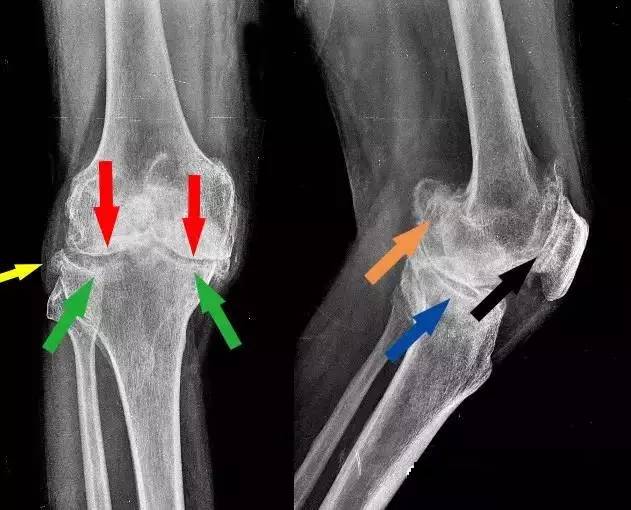

王大爷的片子

医:上图是您右膝的负重正、侧位片,下图是一组正常的膝关节片子。

对比可以看到,您的正位片提示:膝关节骨端明显畸形,内、外侧间隙均变窄甚至消失(红箭头),软骨下骨硬化(绿箭头),关节边缘呈唇样变(黄箭头);侧位片提示:髌股关节骨质增生(黑箭头),后髁骨质增生(橙箭头),胫骨平台骨质囊性变(蓝箭头)。

变窄的关节间隙、几个明显的大骨赘以及周围软组织的挛缩是导致关节活动受限的罪魁祸首。结合临床表现、查体和X片,您诊断为右膝关节重度骨性关节炎,已经到了很严重的程度了!